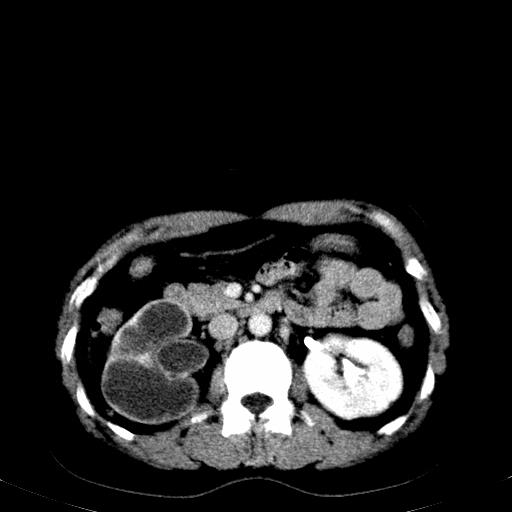

患者体检发现右肾体积增大,怀疑右肾积水

右肾多发囊肿,左肾、左输尿管结石

右肾重度积水,以肾盏积水明显,有分隔,上段输尿管轻度扩张,管壁增厚,考虑肾结核可能,请结合尿检查,胸部拍片排除肺结核。

左肾不像是结石吧,是不是做过造影啊

左肾哪里有结石???

第一个序列应该是延迟图像吧;

结合强化图片看ivp意义不大,建议作逆行造影看一下;

左肾不是结石,是造影后改变.右肾积水,功能仅存.